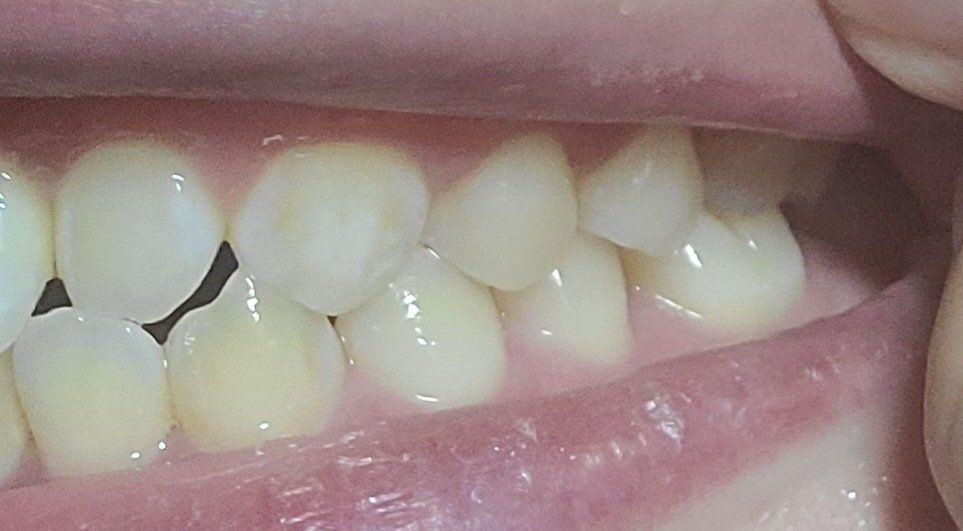

오른쪽1

오른쪽2

왼쪽이 제1소구치쪽부터 교합이 아주 이상적인 교합은 아닙니다. 또한, 오른쪽 2번째 치아는 원래 위 치아가 아래치아를 덮어야하는데, 그렇지 않고 치아끼리 바로 닿습니다. 이 경우 치아에 무리가 갈 수 있습니다.

하지만 사진과 같이 오른쪽 2번째 윗니와 아랫니가 절단교합이 되어 있으면 치아가 다 내려오지 않아서 공간이 보일수 있어요.

왼쪽 소구치와 대구치는 사진으로만 보기에는 정상적으로 교합하고 있는것으로 보입니다.